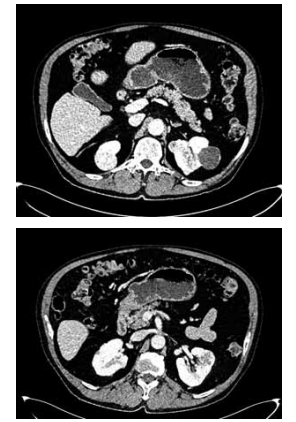

Homem de 65 anos refere hematúria macroscópica há 1 mês. Nega comorbidades ou cirurgias prévias e tem antecedente de cálculos urinários. É tabagista há 40 anos, de um maço por dia. Foi solicitada a tomografia de abdome e pelve, demonstrada a seguir:

Enunciado 4425229-1

(Arquivo pessoal; imagem usada com autorização)

Com essas informações, qual o diagnóstico, uma possível complicação pós-operatória e a medida necessária para reduzir o risco dessa complicação, respectivamente?